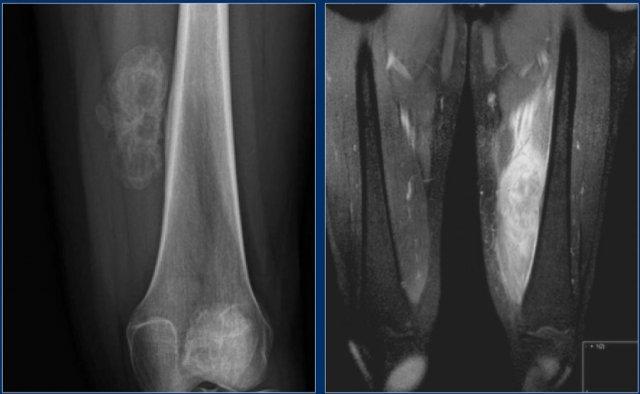

Phim X-quang cho thấy hình ảnh nhồi máu xương điển hình ở thân xương và hành xương của xương đùi và xương chày.

Trên hình ảnh MRI, nhồi máu xương được đặc trưng bởi các bờ không đều dạng rắn bò với tín hiệu thấp trên cả T1 và T2 WI, và tín hiệu mỡ từ trung bình đến cao ở phần trung tâm.

Tăng tín hiệu sau tiêm Gadolinium tĩnh mạch thường tối thiểu hoặc không có (xem hình bên phải).

Ở ngoại vi của ổ nhồi máu có thể thấy một vùng có cường độ tín hiệu tương đối cao trên T2WI.

Việc phân biệt nhồi máu xương với u sụn xương (enchondroma) hoặc u sụn xương ác tính độ thấp (low-grade chondrosarcoma) trên phim X-quang thường có thể rất khó khăn hoặc thậm chí không thể thực hiện được.

Các khối u sụn, đặc biệt là u sụn xương ác tính (chondrosarcoma), có thể biểu hiện hình ảnh xói mòn nội màng xương (endosteal scalloping), trong khi nhồi máu xương thì không có đặc điểm này.

Hình ảnh cho thấy một tổn thương vôi hóa ở đầu gần xương chày mà không có đặc điểm đáng ngờ.

Đây rất có thể là một u sụn nội xương (enchondroma).

Có những đặc điểm khác ủng hộ chẩn đoán sarcoma sụn độ thấp như xạ hình xương dương tính và hình ảnh xói mòn nội màng xương trên MRI (không hiển thị).

Sarcoma sụn đã được chẩn đoán qua sinh thiết.

Đây là hình ảnh X-quang cho thấy các vôi hóa điển hình trong chất nền sụn của u sụn nội xương.

Lưu ý rằng MRI mô tả các tổn thương này một cách dễ dàng như thế nào.